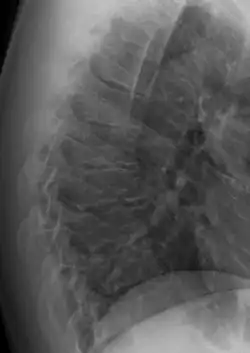

| Scheuermann's disease on lateral Xray of the T spine | |

Scheuermann's disease is a skeletal disorder.[3] It describes a condition where the vertebrae grow unevenly with respect to the sagittal plane; that is, the posterior angle is often greater than the anterior. This uneven growth results in the signature "wedging" shape of the vertebrae, causing kyphosis. It is named after Danish surgeon Holger Scheuermann.[4][5][6]

Scheuermann's disease is considered to be a form of osteochondrosis of the spine. It typically develops during adolescence and presents a significantly worse deformity than postural kyphosis. Patients with Scheuermann’s kyphosis cannot consciously correct their posture. The apex of their curve, located in the thoracic vertebrae, is quite rigid.

Diagnosis is typically by medical imaging. The degree of kyphosis can be measured by Cobb's angle and sagittal balance.